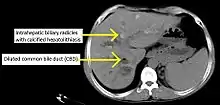

| Cholangiogram of primary sclerosing cholangitis | |

Historically, a cholangiogram would be obtained via endoscopic retrograde cholangiopancreatography (ERCP), which typically reveals "beading" (alternating strictures and dilation) of the bile ducts inside and/or outside the liver. Currently, the preferred option for diagnostic cholangiography, given its noninvasive yet highly accurate nature, is magnetic resonance cholangiopancreatography (MRCP), a magnetic resonance imaging technique. MRCP has unique strengths, including high spatial resolution, and can even be used to visualize the biliary tract of small animal models of PSC.[21]